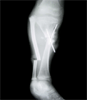

Follow Up

Tibia lenghtening and healing non-union

Final

Result

Complete union and tibia length restored